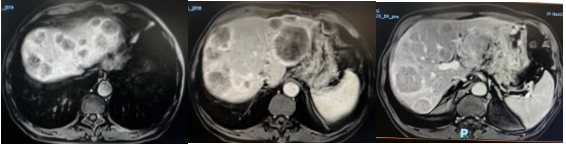

MRI(2018.06.05)示:

1、肝脏异常信号影,考虑肝内多发转移瘤。

2、胃充盈欠佳,胃小弯侧胃壁増厚,需提示占位,建议内镜检查。

3、小弯侧淋巴结,需提示淋巴转移。

上腹部增强MRI(2018-06-05):肝脏异常信号影,考虑肝内多发转移瘤; 胃充盈欠佳,胃小弯侧胃壁増厚,提示占位;小弯侧淋巴结,提示淋巴转移。